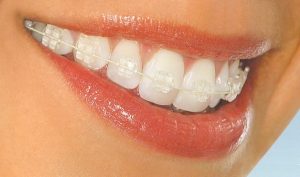

Permanent braces can be: metallic, ceramic, sapphire, incognito and invisalign.

Dental braces with sapphire brackets offer bigger efficiency and optimal results for a perfect smile.